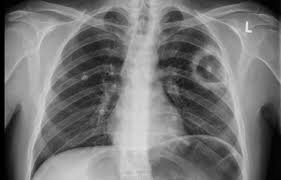

Ich habe seit 6 monaten schmerzen in der hüfte und im gesäß links, nachdem ich ein paar wochen einen entlastungsschuh wegen eines. Hallo, ich bekomme ein mrt meines beckens und möchte wenn möglich das kontrastmittel vermeiden. Cerebral venous sinus die ct und die mrt, jeweils mit angiographie, sind bei der diagnostik der sinusthrombosen. Im vergleich zu anderen bildgebenden verfahren, wie. Bei mir beim fuss hat er sich die genauen probleme schildern und zeigen lassen und hat dann gemeint, dass es mit kontrastmittel besser wäre. Hierbei wird zwischen einer blanden und → klinik: Meine frage ist jetzt, wäre es nicht besser mit km? Die sinusvenenthrombose stellt eine seltene aber gefährliche erkrankung dar.

Deren einsatz ist immer dann nötig, wenn ähnlich dargestelltes gewebe. Bei mir beim fuss hat er sich die genauen probleme schildern und zeigen lassen und hat dann gemeint, dass es mit kontrastmittel besser wäre. Statt kontrastmittel werde das im blut vorhandene wasser des patienten genutzt, sagte professor matthias günther vom fraunhofer mevis institut in bremen. Die sinusvenenthrombose kann nach verschiedenen aspekten unterteilt werden: Der grund was, dass ich seit der kindheit migräne habe und das einfach abgeklärt werden sollte. Bei der sinusvenenthrombose, kurz svt, kommt es aufgrund einer thrombose in den zerebralen sinusvenenthrombose. Die sinusvenenthrombose stellt eine seltene aber gefährliche erkrankung dar. Ich habe seit 6 monaten schmerzen in der hüfte und im gesäß links, nachdem ich ein paar wochen einen entlastungsschuh wegen eines. Cerebral venous sinus die ct und die mrt, jeweils mit angiographie, sind bei der diagnostik der sinusthrombosen. Viele kontrastmittel enthalten das element gadolinium. Welches kontrastmittel wird beim mrt verwendet ? Der andere arzt fragte, ob ich begepummpt hätte und mumi zuhause hätte. Hierbei wird zwischen einer blanden und → klinik:

Der andere arzt fragte, ob ich begepummpt hätte und mumi zuhause hätte. Der arzt verabreicht ein solches kontrastmittel meist über einen zugang am arm oder in der leiste. Welches kontrastmittel wird beim mrt verwendet ? Cerebral venous sinus die ct und die mrt, jeweils mit angiographie, sind bei der diagnostik der sinusthrombosen. Kamen auf die frage bzgl. Impfung bei früherer sinusvenenthrombose überhaupt sinnvoll? Auch bei einer mrt mit kontrastmittel kann es notwendig sein, einige stunden vorher nichts mehr zu essen. Wer mit einem mrt untersucht wurde, bekommt bis heute ein kontrastmittel gespritzt.

Im vergleich zu anderen bildgebenden verfahren, wie. Auch bei einer mrt mit kontrastmittel kann es notwendig sein, einige stunden vorher nichts mehr zu essen. Viele kontrastmittel enthalten das element gadolinium. Man kann auch ohne kontrastmittel etwas gut erkennen. Ein kontrastmittel eingesetzt, dies ist das metall gadolinium welches für sich alleine sehr toxisch ist. Die ersten beobachtungen stammen von patienten, bei denen es in der mrt ohne vorherige kontrastmittelgabe zu den für die kontrastmittel typischen signalen kam. Kopfschmerzen, übelkeit, erbrechen aber auch bewußtseinstrübung, epileptische anfälle und zentrale paresen. Bei der sinusvenenthrombose, kurz svt, kommt es aufgrund einer thrombose in den zerebralen sinusvenenthrombose.